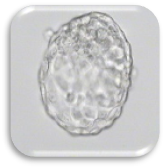

การเลี้ยงตัวอ่อนถึงระยะบลาสโตซีสต์ (BLASTOCYST CULTURE)

ปัจจุบันนี้ได้มีการพัฒนาน้ำยาเพาะเลี้ยงตัวอ่อน ให้สามารถเลี้ยงได้ถึงในระยะBLASTOCYST ซึ่งส่งผลให้สามารถคัดเลือกและประเมินตัวอ่อนได้ดีขึ้น ดังนั้นถ้าเราสามารถเลี้ยงตัวอ่อนได้ถึงระยะ BLASTOCYST เราก็อาจจะใส่ตัวอ่อนจำนวนน้อยลง เพื่อเป็นการลดอุบัติการณ์การตั้งครรภ์แฝด

ตัวอ่อนระยะบลาสโตซิสต์ (Blastocyst : Day 5-6)